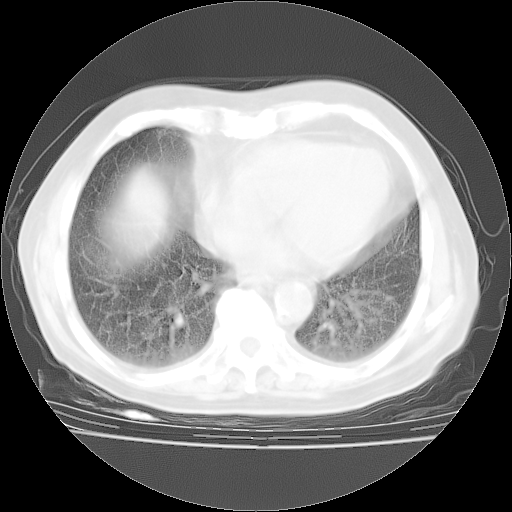

4月28日肺部CT——再次出现类似去年5月9日——磨玻璃样、间有“粟粒样”改变。

个人阅读4.14日肺部CT平扫:纵隔窗无异常,但肺窗示:双下肺内、后基底段有片絮状侵润影,部位以后基底段为著,以间质改变为主,呈急性肺泡炎征像,和首次住院影像学有相似之处。仅是个人读片,明日请相关专家再读片哈。其它建议同上。

今请临免主任会诊后认为:4月14日胸部CT已有双下肺间质性改变。患者病情复发多系激素减量过快不正规所致。目前甲强龙80mg/日,一周后酌情开始减量,不易过快。环磷酰胺若已停用,暂不使用。他同意目前抗菌药物使用,但应考虑是否加用B-内酰胺类抗菌药物(中性细胞明显增高);2、结核复发目前依据不足;3、若免疫全套各项指标正常,考虑多系特发性肺间质炎可能大。4、加强支持,并注意保护胃黏膜。

今上午去请教了临免、呼吸主任:1、介绍病史和阅读系列胸部CT一致认为:患者肺结核不考虑,仍为肺间质纤维化,目前处于急性肺泡炎阶段。2、若仍发热,可将甲强龙增至:80mg Bid静滴,同时鉴于中性增高,合并细菌感染可能,继续左氧氟沙星治疗,再联用B-内酰胺抗菌药物,如头孢哌酮--舒巴坦;3、停用抗痨药;4、目前甲强龙每日剂量160mg ,体温正常后再酌情减量;目前暂不用免疫抑制剂;4、不建议使用免疫增强剂等;5、加强支持治疗,鼓励患者进食;5、注意随访肝、肾功及血常规情况;6、因患者目前激素用量较大,加用胃黏膜保护剂,防止消化道出血可能。